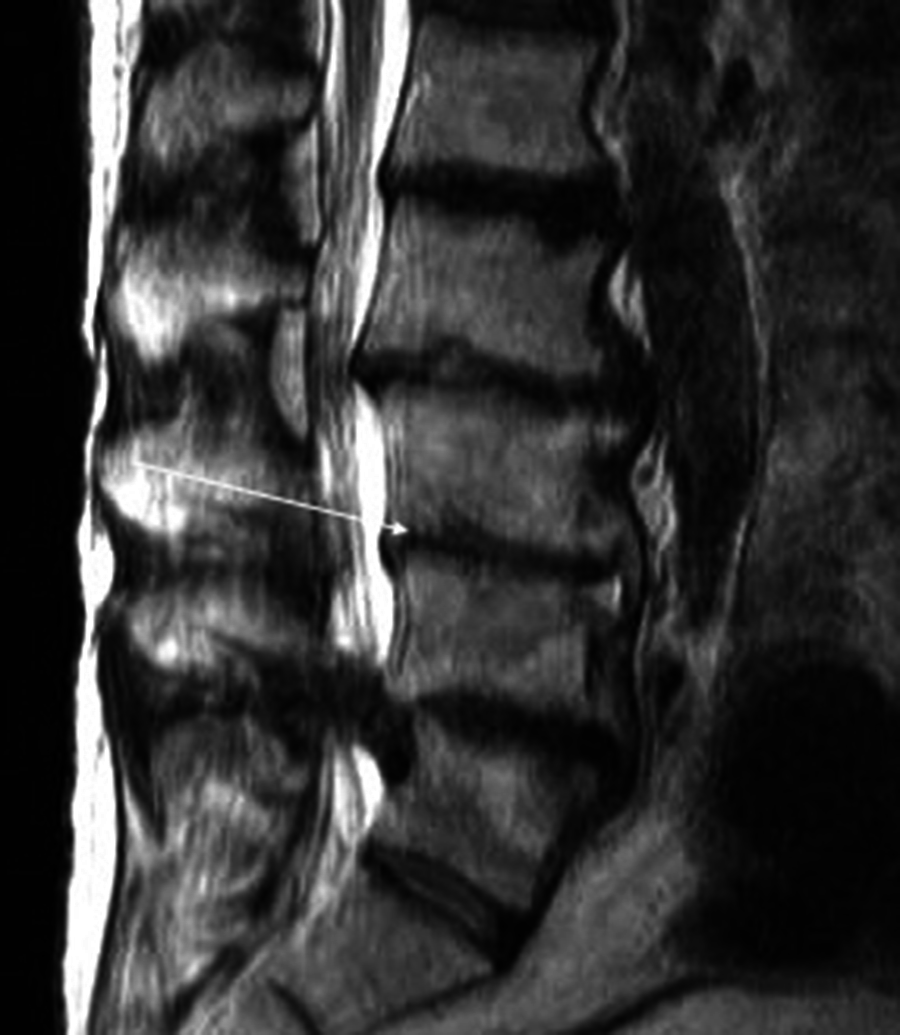

Plain radiographs revealed degenerative changes without evidence of fracture (Figure 1). Magnetic resonance imaging (MRI) raised the suspicion of osteomyelitis involving L2-3 and L3-4 with a possible abscess in the L3-4 disk space (Figure 2). A computerized tomography (CT)-guided biopsy provided tissue which registered positive cultures for Candida glabrata resistant to fluconazole, itraconazole, and posaconazole, but sensitive to micafungin and amphotericin B. No anaerobes, acid-fast bacilli, or aerobic organisms were present in the bioptic material.